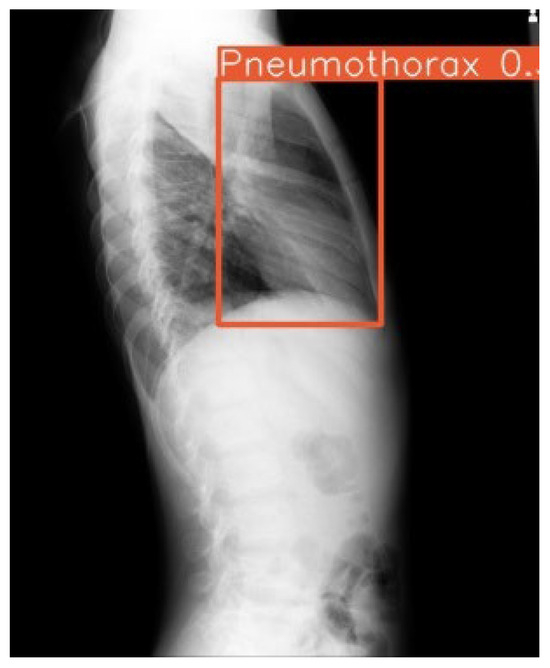

Diagnostic Accuracy of an Offline CNN Framework Utilizing Multi-View Chest X-Rays for Screening 14 Co-Occurring Communicable and Non-Communicable Diseases

Background: Chest radiography is the most widely used diagnostic imaging modality globally, yet its interpretation is hindered by a critical shortage of radiologists, especially in low- and middle-income countries (LMICs). The interpretation is both time-consuming and error-prone in high-volume settings. Artificial Intelligence (AI) [...] Read more.

Background: Chest radiography is the most widely used diagnostic imaging modality globally, yet its interpretation is hindered by a critical shortage of radiologists, especially in low- and middle-income countries (LMICs). The interpretation is both time-consuming and error-prone in high-volume settings. Artificial Intelligence (AI) systems trained on public data may lack generalizability to multi-view, real-world, local images. Deep learning tools have the potential to augment radiologists by providing real-time decision support by overcoming these. Objective: We evaluated the diagnostic accuracy of a deep learning-based convolutional neural network (CNN) trained on multi-view, hybrid (public and local datasets) for detecting thoracic abnormalities in chest radiographs of adults presenting to a tertiary hospital, operating in offline mode. Methodology: A CNN was pretrained on public datasets (Vin Big, NIH) and fine-tuned on a local dataset from a Nepalese tertiary hospital, comprising frontal (PA/AP) and lateral views from emergency, ICU, and outpatient settings. The dataset was annotated by three radiologists for 14 pathologies. Data augmentation simulated poor-quality images and artifacts. Performance was evaluated on a held-out test set (N = 522) against radiologists’ consensus, measuring AUC, sensitivity, specificity, mean average precision (mAP), and reporting time. Deployment feasibility was tested via PACS integration and standalone offline mode. Results: The CNN achieved an overall AUC of 0.86 across 14 abnormalities, with 68% sensitivity, 99% specificity, and 0.93 mAP. Colored bounding boxes improved clarity when multiple pathologies co-occurred (e.g., cardiomegaly with effusion). The system performed effectively on PA, AP, and lateral views, including poor-quality ER/ICU images. Deployment testing confirmed seamless PACS integration and offline functionality. Conclusions: The CNN trained on adult CXRs performed reliably in detecting key thoracic findings across varied clinical settings. Its robustness to image quality, integration of multiple views and visualization capabilities suggest it could serve as a useful aid for triage and diagnosis. Full article

Show Figures

Figure 1